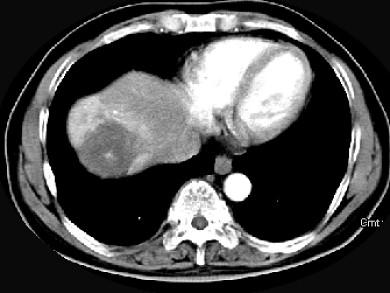

问题 男性,54岁,右上腹部不适,CT检查如图,最可能的诊断是 ( )

选项 A、肝血管瘤伴肝脓肿 B、肝血管瘤伴炎性肉芽肿 C、肝多发血管瘤 D、肝血管瘤伴肝癌 E、肝血管瘤伴转移瘤

答案 C